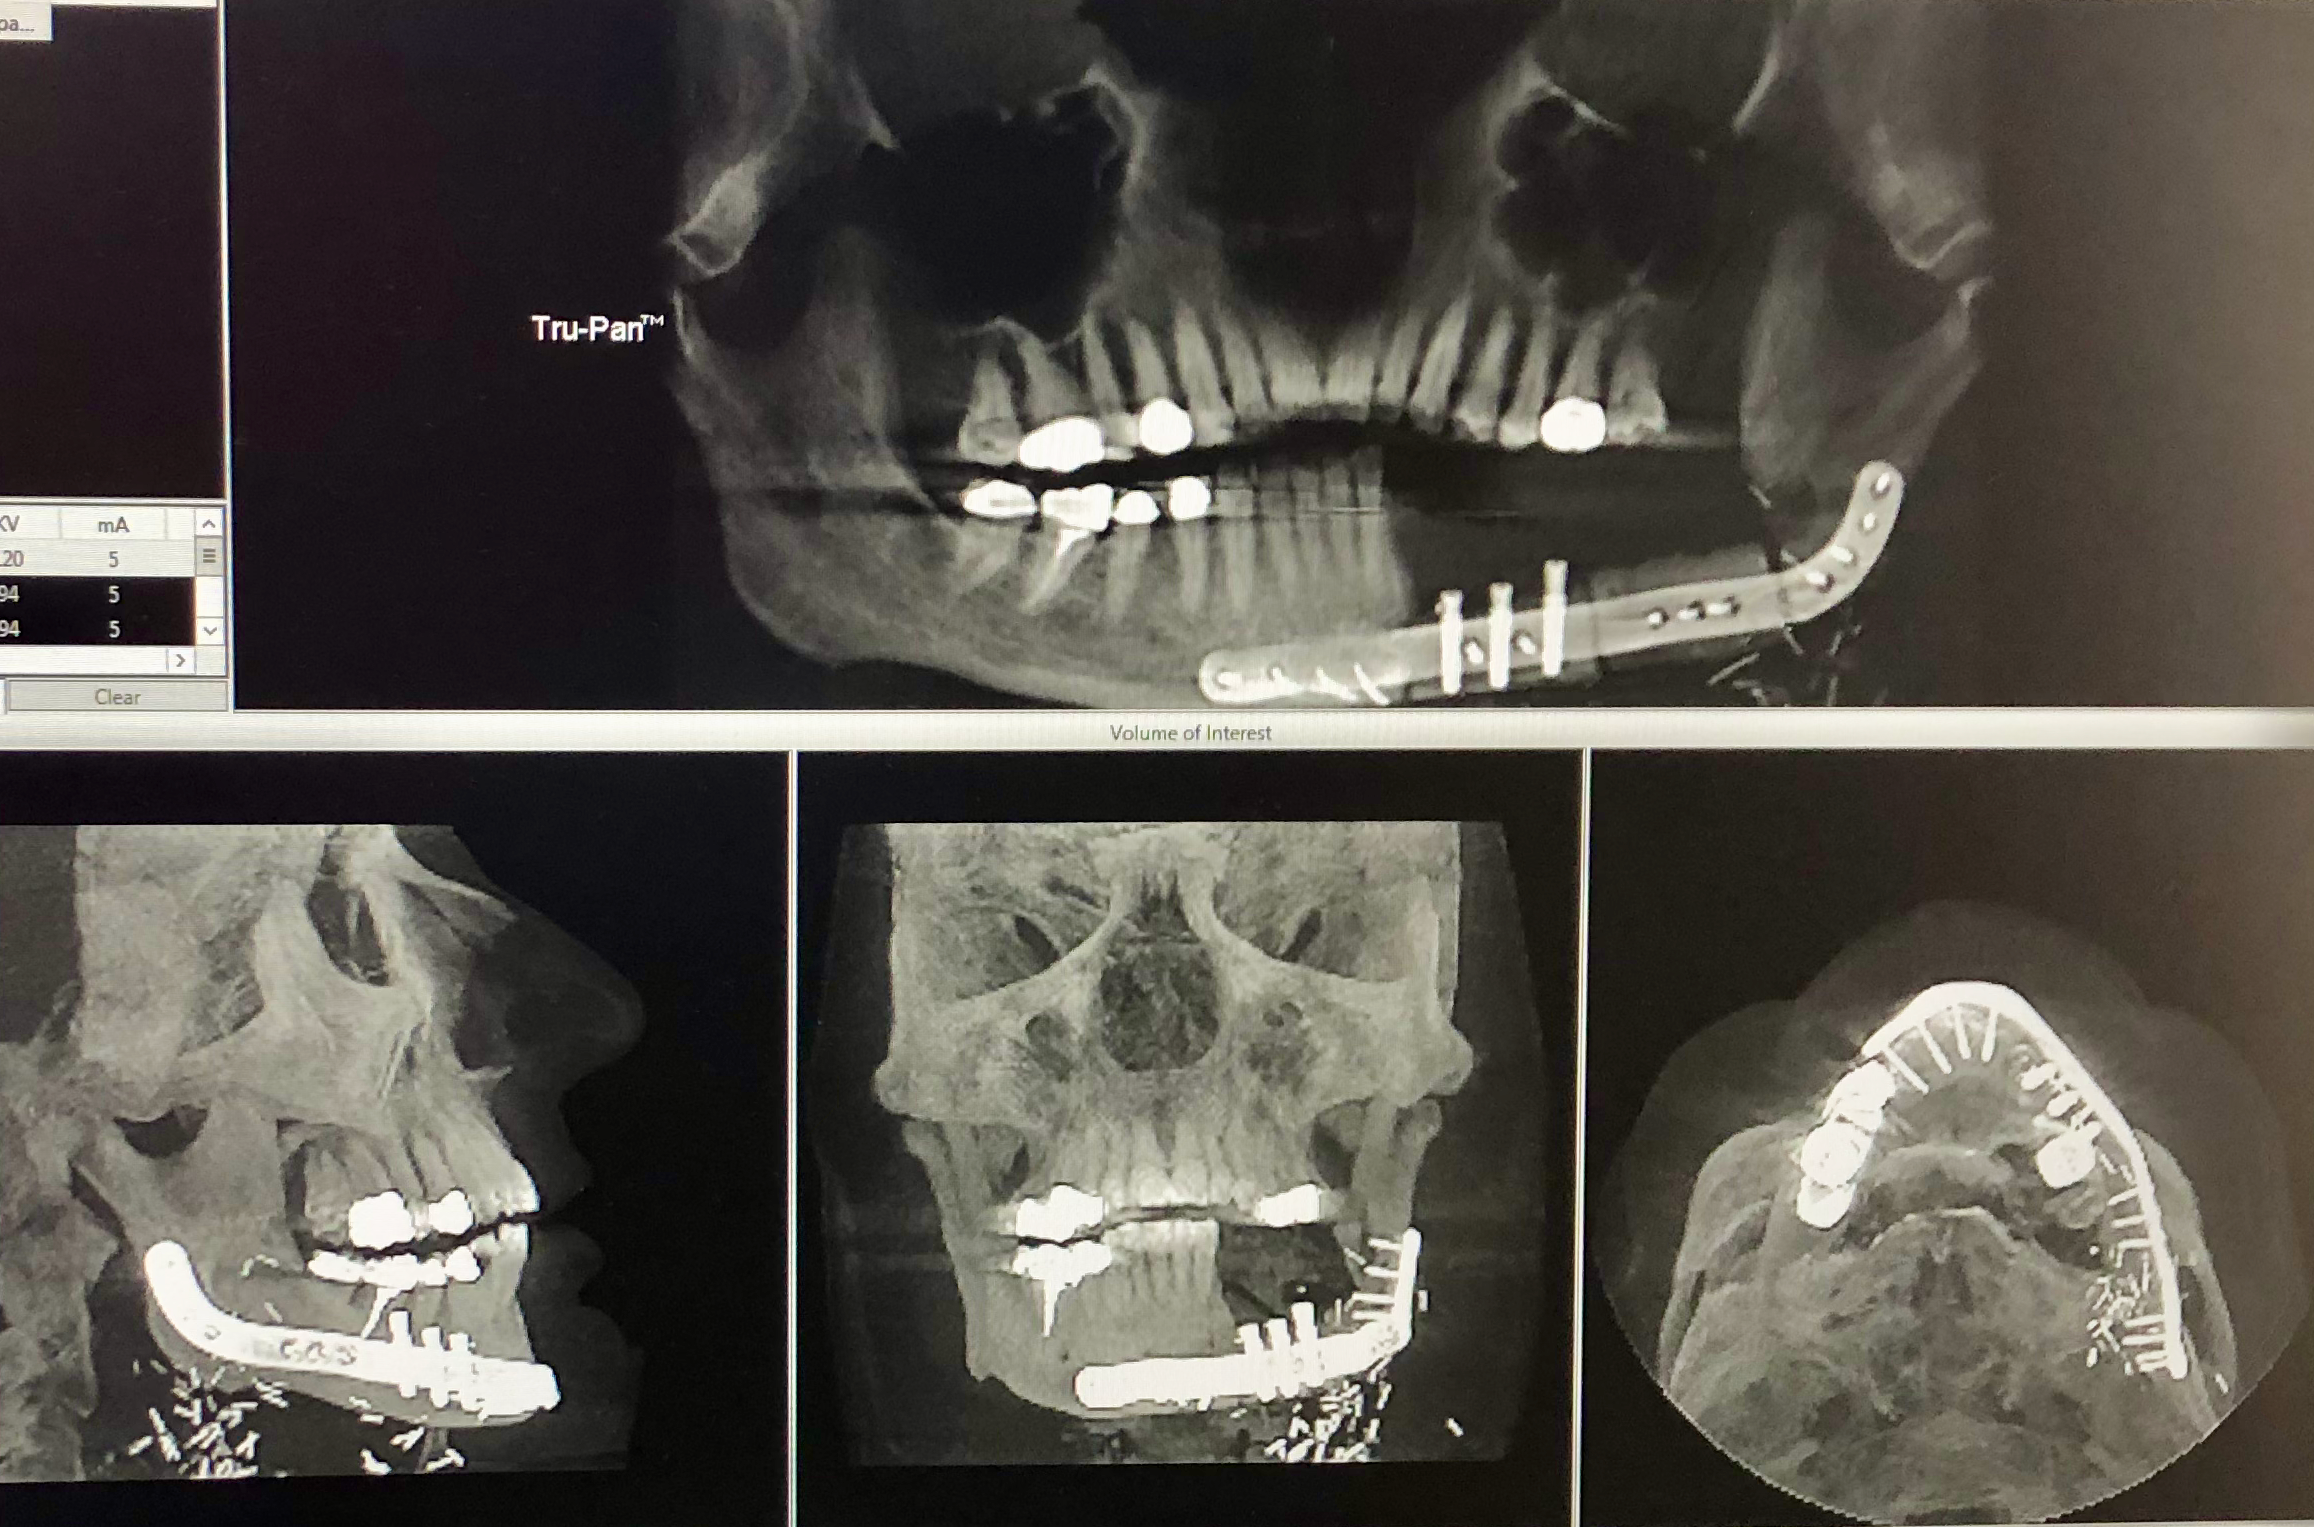

Last week I saw Dr. Garvey, the plastic surgeon and he was very pleased with progress and thought it was time to touch base with dental in preparation for getting teeth fitted. I now have a date for oral surgery to expose the implants and begin the dental work. I’ll have a prosthetic, with 5 teeth, which will clip onto the implant abutments. Surgery date is 27th November – the day before Thanksgiving, so no dinner for me this year. However, that means I may have a full compliment of teeth by the end of the year. As. You can see above, we got to see X-rays of my jaw and all the hardware in there! I had no idea!! It seems the implants were put into the bone before it was cut from my leg – all done using a 3D computer model to get it all in the right place!